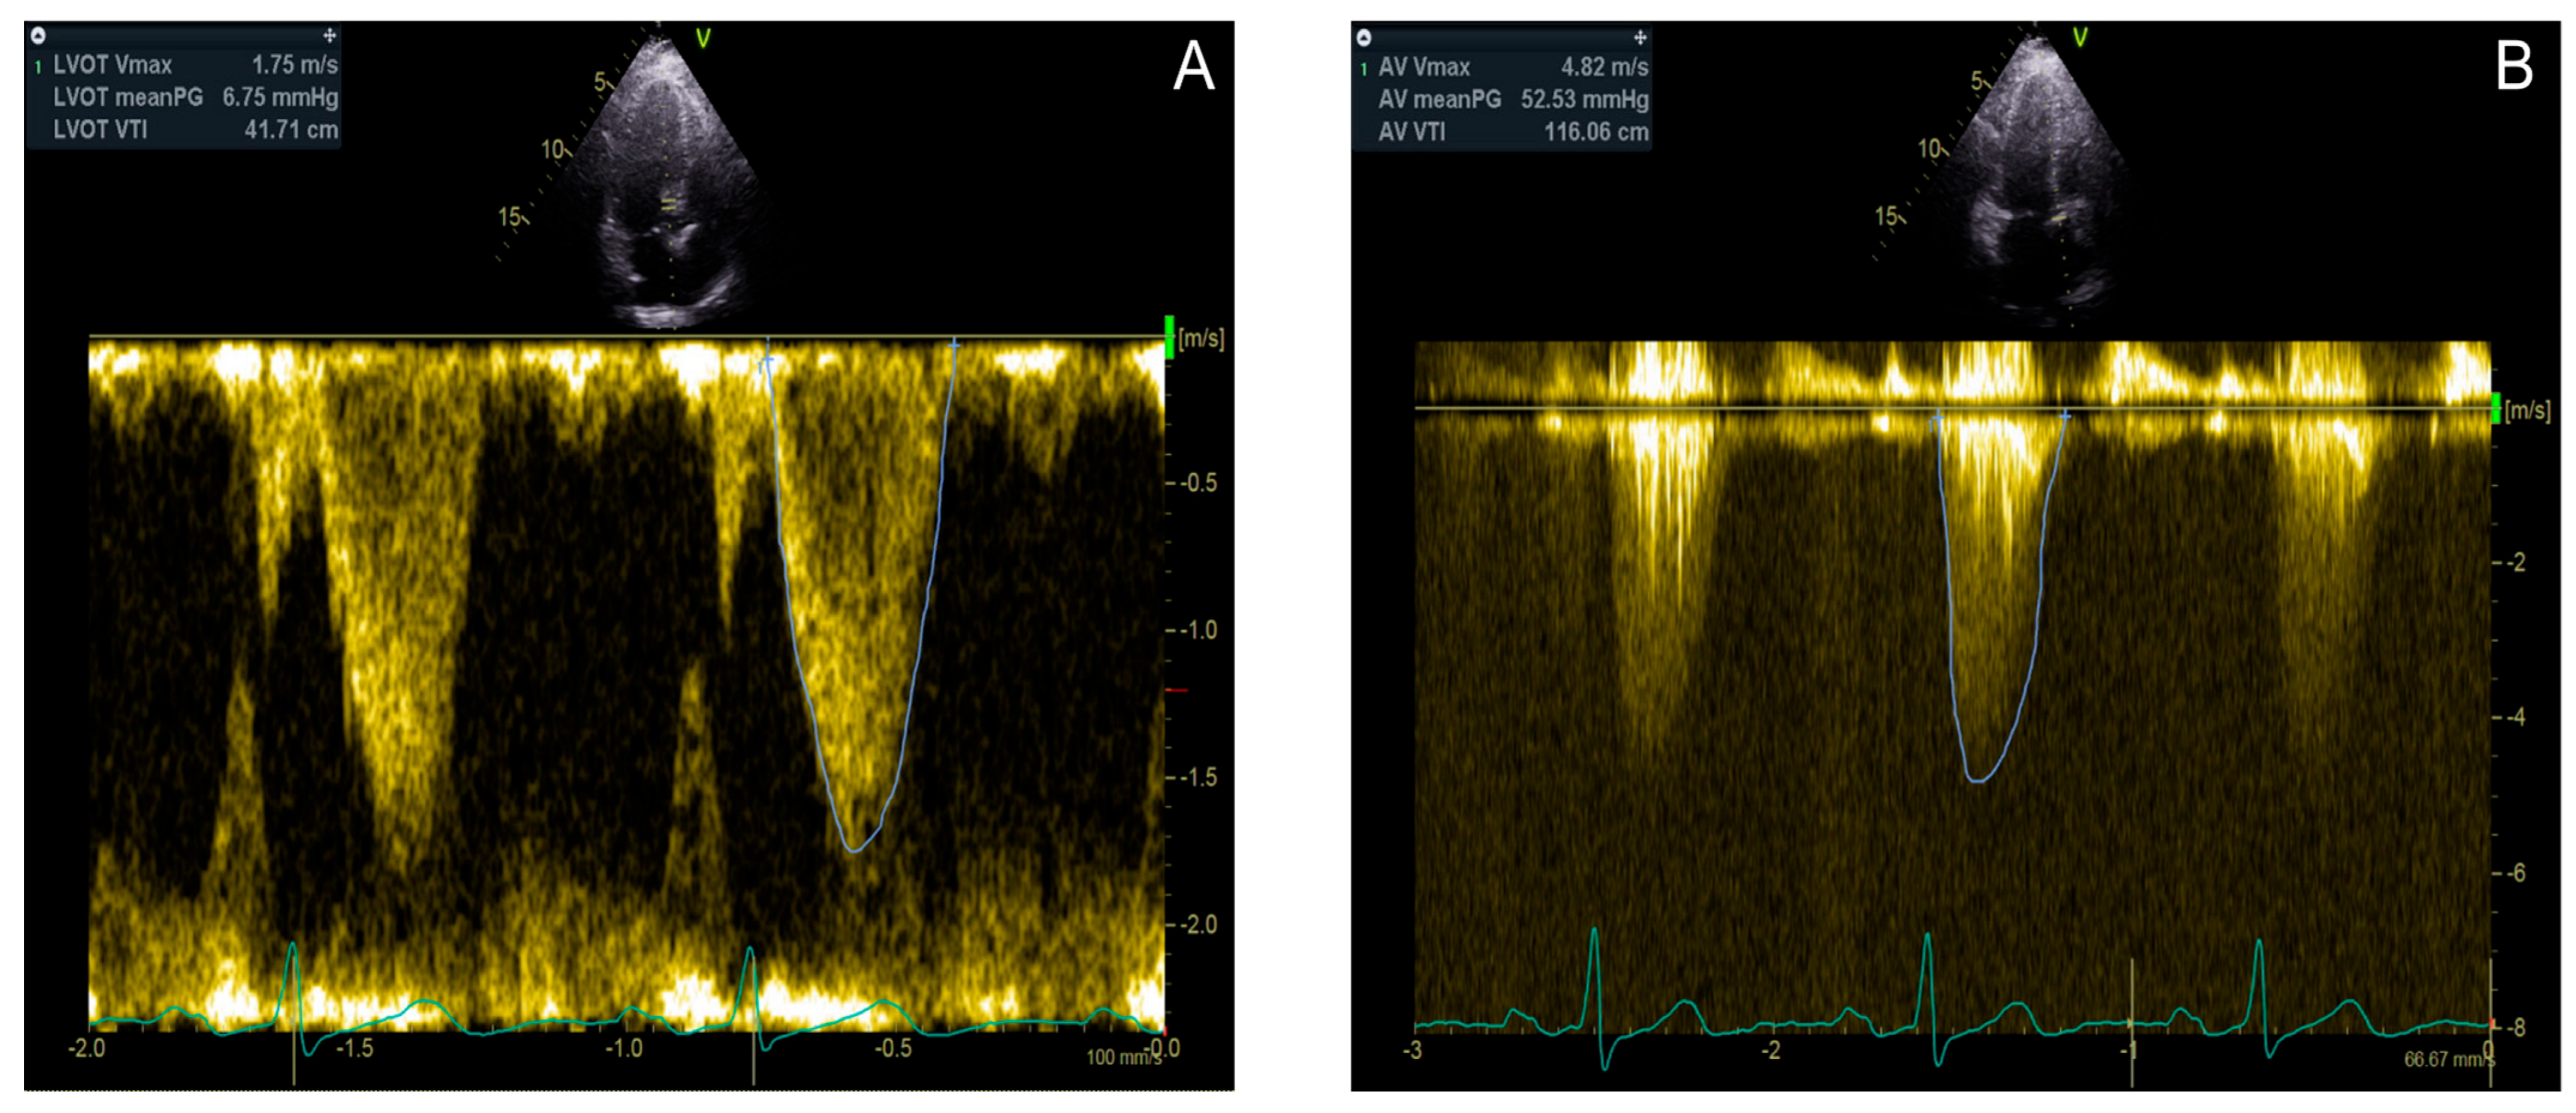

Figure 4. An 80 year old female patient with discordant high gradient aortic stenosis. Left ventricle outflow tract diameter VTI is 41.71 cm (A); aortic valve VTI is 116.06 cm, and mean gradient is 52.53 mmHg (B). The LVOT diameter is 2.21 cm. According to these measurements, cardiac output is 9.97 L/min, cardiac index is 5.63 L/min/m2, and the aortic valve area by VTI is 1.38 cm2.